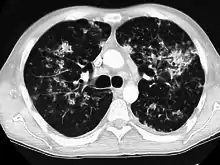

A case of miliary tuberculosis in an 82-year-old woman:

X-ray, 13 days after onset, showing bilateral interstitial infiltrates

CT, 16 days after onset, showing extensive pulmonary parenchymal involvement consisting of irregular septal thickenings with ground-glass areas and centrilobular nodules with a peri-lymphatic distribution

X-ray, 22 days after onset, showing extensive bilateral reticulo-nodular infiltrates